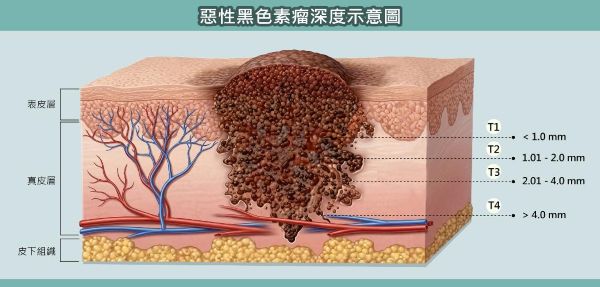

惡性黑色素瘤若能在早期發現並接受手術切除,第 1 期患者 5 年存活率可達 85% 以上;但若進展至第 4 期,存活率則可能降至 20%。高醫整形外科黃書鴻教授提醒民眾,平時可定期檢視手掌、指甲、腳底、腳背與腳趾等部位,若發現黑點或色素變化,應先記錄並持續觀察;一旦出現大小、形狀或顏色改變,或有隆起、破皮、易出血等情況,務必及早就醫檢查,以免錯過治療黃金期。

圖說2:婦人的腫瘤深度已超過 4mm 並侵入至皮下組織。所幸透過正子掃描(PET)與前驅淋巴結切片手術確認,癌細胞尚未發生淋巴結及遠端器官轉移。